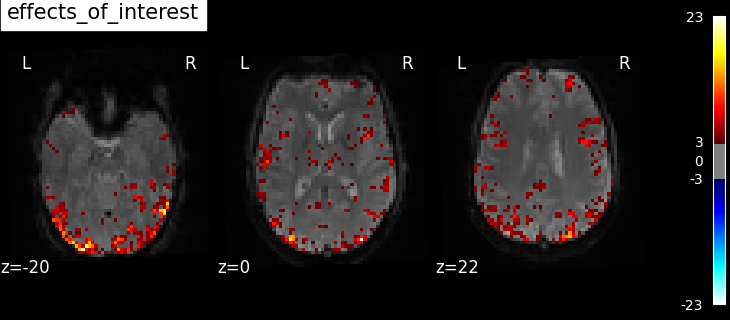

Now we can compute contrast-related statistical maps (in z-scale), and plot them.

for contrast_id, contrast_val in contrasts.items():

z_map = fmri_glm.compute_contrast(contrast_val, output_type="z_score")

plotting.plot_stat_map(

z_map,

bg_img=mean_image,

threshold=3.0,

display_mode="z",

cut_coords=3,

black_bg=True,

title=contrast_id,

)

contrast id: effects_of_interest

Based on the resulting maps we observe that the analysis results in wide activity for the ‘effects of interest’ contrast, showing the implications of large portions of the visual cortex in the conditions. By contrast, the differential effect between “faces” and “scrambled” involves sparser, more anterior and lateral regions. It also displays some responses in the frontal lobe.